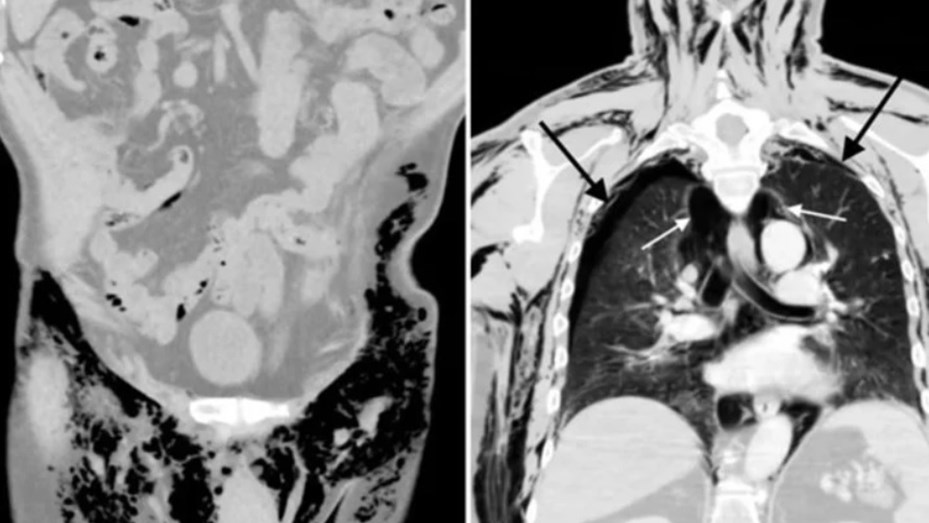

Análisis posteriores le detectaron un neumoescroto silbante, neumotórax bilateral, neumomediastino y enfisema subcutáneo.

Si bien no tuvo complicaciones al principio, tiempo después se le detectó un neumoescroto silbante, así como otras patologías derivadas de la acumulación de aire en el tórax.

Los análisis al paciente arrojaron también un neumotórax bilateral, una acumulación de aire en una cavidad entre los pulmones y el tórax conocida como cavidad pleural.

Asimismo, le detectaron neumomediastino, que se debe también a una acumulación del aire, esta vez en una cavidad ubicada entre los dos pulmones.

Y, por último, le diagnosticaron un enfisema subcutáneo a raíz de la penetración de aire en los tejidos ubicados bajo la piel.